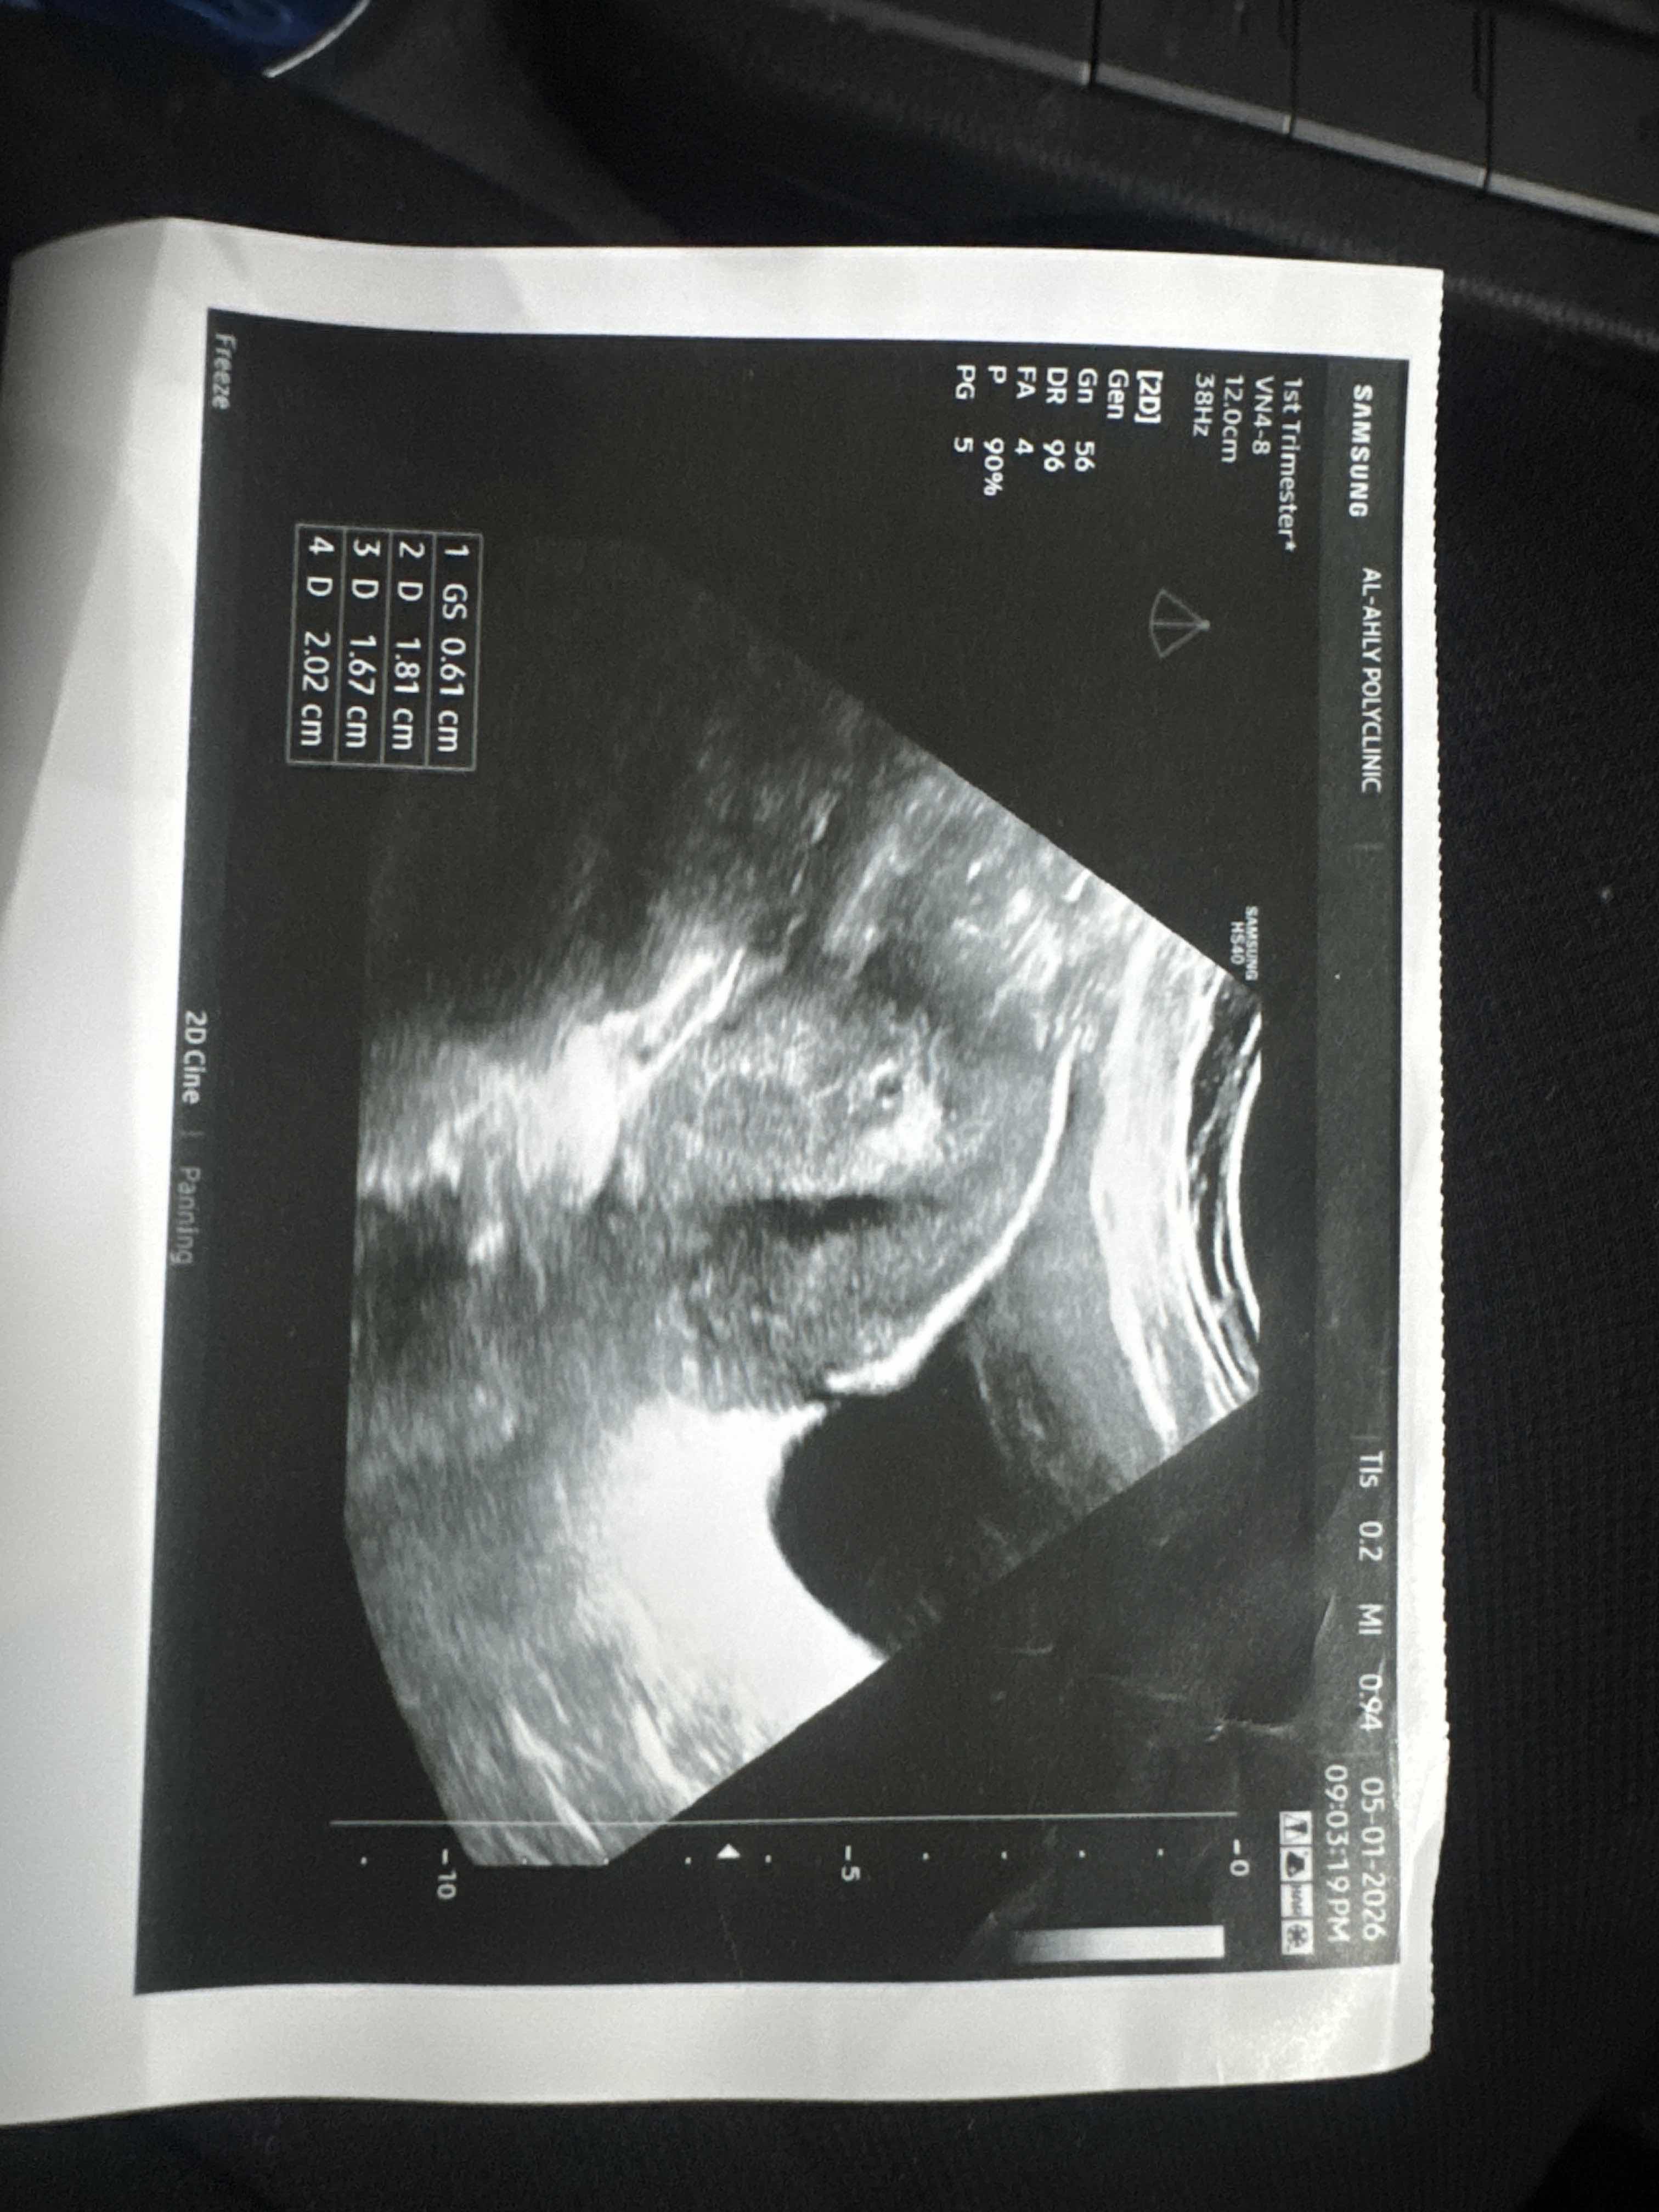

اليوم 18 من ارجاع الاجنه

نعم ...جيدة وتابعي